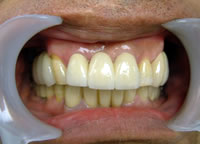

14.上は作った最終本物の歯が入っています。

16.上は仕上がりが入り、下は仮歯です。

19.下は作った最終本物の歯が入りました。

これで治療終了。

開口器を入れた口元

治療完了

平成21年1月29日

(治療期間:1年7ヶ月)